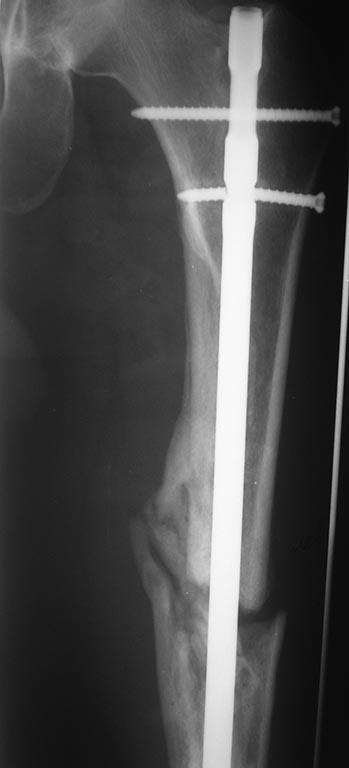

Добрый день уважаемые коллеги. Вашему вниманию представляю пациента(мужчина, 30 лет). Тяжелая сочетанная травма 7 мес. назад. Из скелетной травмы: открытый перелом бедра, открытый перелом дистального метаэпифиза левого плеча, закрытый перелом шейки левого плеча). Все повреждения были прооперированы. Бедро синтезировано штифтом Остеомед d-11мм. Раны зажили первично. Пациент после выписки впервые появился на контрольный осмотр ч/з 7 месяцев. Жалобы на боли в левом бедре при нагрузке, ощущение подвижности в месте перелома. Передвигается без дополнительных средств опоры. Локально: отека левого бедра нет, п/операционные рубцы без признаков воспаления. движения в суставах левой н/конечности в полном объеме, безболезненны.( все снимки, первичные, после операции и на сегодня прилагаю). основной вопрос, тактический, чем лучше выполнить реостеостеосинтез. У нас в наличии имеется: из штифтов Остеомед d-12мм, старый набор Синтез с канюлированными штифтами максимальный d-14мм., пластины LC-DCP, аппарат Илизарова. В плане 2 варианта: 1) удаление проксимальных блокирующих винтов(сломаный тоже), фиксация бедра спице-стержневым аппаратом из 2-х опор и компрессия в аппарате. 2)удаление металлоконструкции, и выполнение реостеосинтеза с рассверливанием( учитывая очень широкий канал) с установкой винтов поллеров в дистальном отломке. Жду ваших предложений и мнений. Спасибо заранее

С возросшей регулярностью на форуме обсуждаются «беспричинные» случаи несращения переломов после интерлокинга. В постах больше внимания уделяется обсуждению тактике дальнейшего лечения. Причём в подобных случаях предлагаемые варианты не отличаются многообразием и ограничиваются либо таким же остеосинтезом только стержнем большего диаметра, либо пластинкой с костной пластикой либо внеочаговой фиксацией. К сожалению, почти всегда остаются без анализа возможные причины, приведшие к несращению. А жаль. Ведь вероятность сращения после интерлокинга приближается к ста процентам, и точно установленная причина, почему это не произошло в положенные сроки, может подсказать тактику дальнейшего лечения. С моей точки зрения, безусловной причиной несращения перелома бедренной кости в обсуждаемой случае является оставшаяся подвижность между проксимальным и дистальными фрагментами после остеосинтеза. На это указывает и сам больной. Причём очаг нестабильности расположен в проксимальном костном фрагменте между ним и проксимальным концом стержня. Хотя на первый взгляд кажется, что вся проблема в дистальном костном отломке, точнее в отсутствии стабильности между ним и дистальным концом стержня из-за значительной разницы в диаметрах стержня и костномозгового канала. На последних рентгенограммах чётко видна костная мозоль между латеральным кортикальным слоем и стержнем на входе в костномозговой канал дистального отломка. Она говорит об эффективности дистального блокирования тремя блокирующими винтами в полифокальных плоскостях. И на сегодня биомеханическая система дистальный отломок – стержень работает как единое целое. Формируется новый костномозговой канал в дистальном отломке по ходу дистального конца стержня за счёт образования костной мозоли между латеральным кортикальным слоем и стержнем. И этот формирующийся костномозговой канал точно соответствует диаметру стержня, что является дополнительным фактором, стабилизирующим дистальный конец стержня. Поэтому, с моей точки зрения, не имеют смысла предложения, направленные на введение каких-либо металлоконструкций, уменьшающих размер костномозгового канала дистального отломка. Да и сделать это технически при такой рентгенологической картине крайне сложно, если вообще возможно. Что касается проксимального блокирования. Крайне неудачно проведен самый проксимальный блокирующий винт. Если авторы рассчитывали на последующую динамизацию (что, при таком переломе крайне неразумно), то его надо было проводить по верхнему краю овального отверстия. Если предполагалось статическая фиксация на протяжении всего периода сращения, то было бы разумнее его провести по нижнему краю овального отверстия. Тогда нагрузка при передвижении больного распределялась бы на оба проксимальных блокирующих винта, что снизило бы вероятность их перелома. Я уже писал в предыдущих постах с похожими случаями. Два блокирующих винта во фронтальной плоскости, один из которых проведен через овальное отверстие, не могут обеспечить стабильность во фронтальной плоскости, если костномозговой канал на выходе из проксимального отломка не соответствует диаметру стержня. И это, с моей точки зрения, служит наиболее частой причиной несращения. И это же служило причиной частых несращений при фиксации тонкими стержнями без рассверливания костномозгового канала. В данном случае мы бы рассверлили канал до диаметра канала на выходе из проксимального отломка (13-14 мм) и имплантировали бы стержень такого же диаметра как последнее сверло. Отдаю предпочтение протезированию всей длины бедренной кости с дистальным блокирование в мыщелках. Лучший вариант, с моей точки зрения, – реконструктивный стержень с проксимальным блокированием в шейке бедра двумя винтами. Хотя допустим и обычный стержень с расположением винта в овальном отверстии по его нижнему краю. Режим фиксации, безусловно, статический.

Непохоже. Вверху он нормально держался, и внизу центрального отломка канал неширокий. Подвижность явно была, но скорее всего, больше за счет расколотого и длинного периферического отломка, винты-то далеко, а рычаг длинный. В сочетании с неустранненным смещением по ширине, отсутствием кортикальной аппозиции по латеральной стенке даже достаточно активного костеобразования здесь не хватило, чтобы стабилизировать отломки.